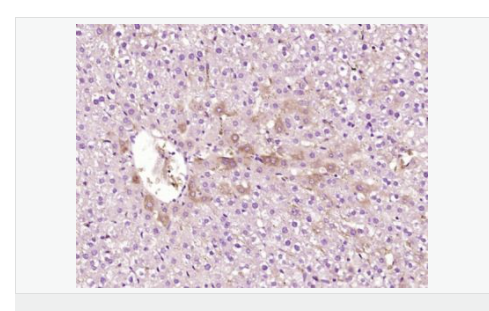

| 產(chǎn)品應用 | WB=1:500-2000 ELISA=1:5000-10000 IHC-P=1:100-500 IHC-F=1:100-500 IF=1:100-500 (石蠟切片需做抗原修復) not yet tested in other applications. optimal dilutions/concentrations should be determined by the end user. |

| 產(chǎn)品介紹 | ATP7b is an important protein for copper transport and elimination of excess copper from the body. ATP7b transports metals in and out of cells using ATP. There are 3 known isoforms of the ATP7b gene; A is found in the liver, kidney, and brain, the shorter form B is found in brain tissue, and the third isoform, known as WND/140 KDA is found in mitochondria. Mutations in the ATP7b gene can cause Wilson's disease, an inherited disorder causing copper poisoning in the brain and liver. Function: Involved in the export of copper out of the cells, such as the efflux of hepatic copper into the bile. Subunit: Monomer. Interacts with COMMD1/MURR1. Subcellular Location: Golgi apparatus, trans-Golgi network membrane; Multi-pass membrane protein. Isoform 2: Cytoplasm. WND/140 kDa: Mitochondrion. Tissue Specificity: Most abundant in liver and kidney and also found in brain. Isoform 2 is expressed in brain but not in liver. The cleaved form WND/140 kDa is found in liver cell lines and other tissues. Post-translational modifications: Isoform 1 may be proteolytically cleaved at the N-terminus to produce the WND/140 kDa form. DISEASE: Defects in ATP7B are the cause of Wilson disease (WD) [MIM:277900]. WD is an autosomal recessive disorder of copper metabolism in which copper cannot be incorporated into ceruloplasmin in liver, and cannot be excreted from the liver into the bile. Copper accumulates in the liver and subsequently in the brain and kidney. The disease is characterized by neurologic manifestations and signs of cirrhosis. Similarity: Belongs to the cation transport ATPase (P-type) (TC 3.A.3) family. Type IB subfamily. Contains 6 HMA domains. SWISS: P35670 Gene ID: 540 Database links: Entrez Gene: 540 Human Omim: 606882 Human SwissProt: P35670 Human Unigene: 492280 Human Important Note: This product as supplied is intended for research use only, not for use in human, therapeutic or diagnostic applications. 銅轉(zhuǎn)運蛋白質(zhì)β鏈是銅轉(zhuǎn)運蛋白質(zhì)家族中的一種,可調(diào)節(jié)細胞內(nèi)銅離子水平的銅轉(zhuǎn)運P型三磷酸腺苷酶,ATP7B是生物體內(nèi)廣泛存在的一種極為重要的細胞膜上的酶,它的功能主要是維持細胞內(nèi)外的離子及滲透壓平衡、跨膜電化學和細胞的能量代謝. |